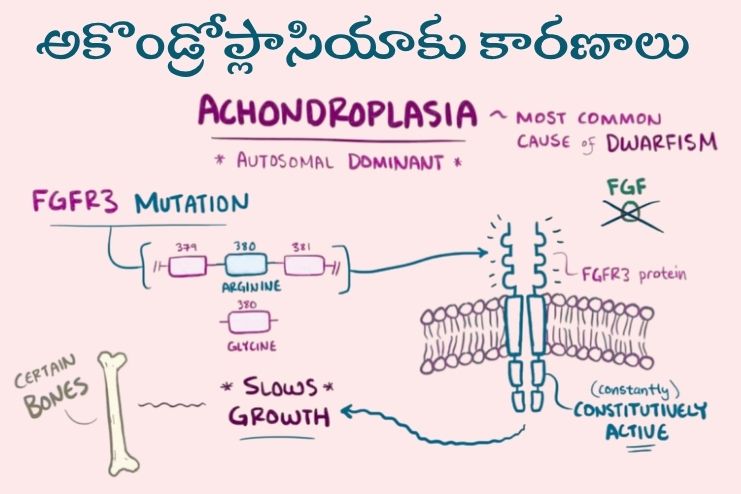

అకొండ్రోప్లాసియాకు కారణాలు? What causes achondroplasia?

పిండం అభివృద్ధి చెందుతున్నప్పుడు మృదులాస్థిని ఎముకగా మార్చే గ్రాహకంలో (రిసెప్టర్లో) జన్యు మార్పు (మ్యుటేషన్) జరగడం వల్ల అకొండ్రోప్లాసియా వస్తుంది.